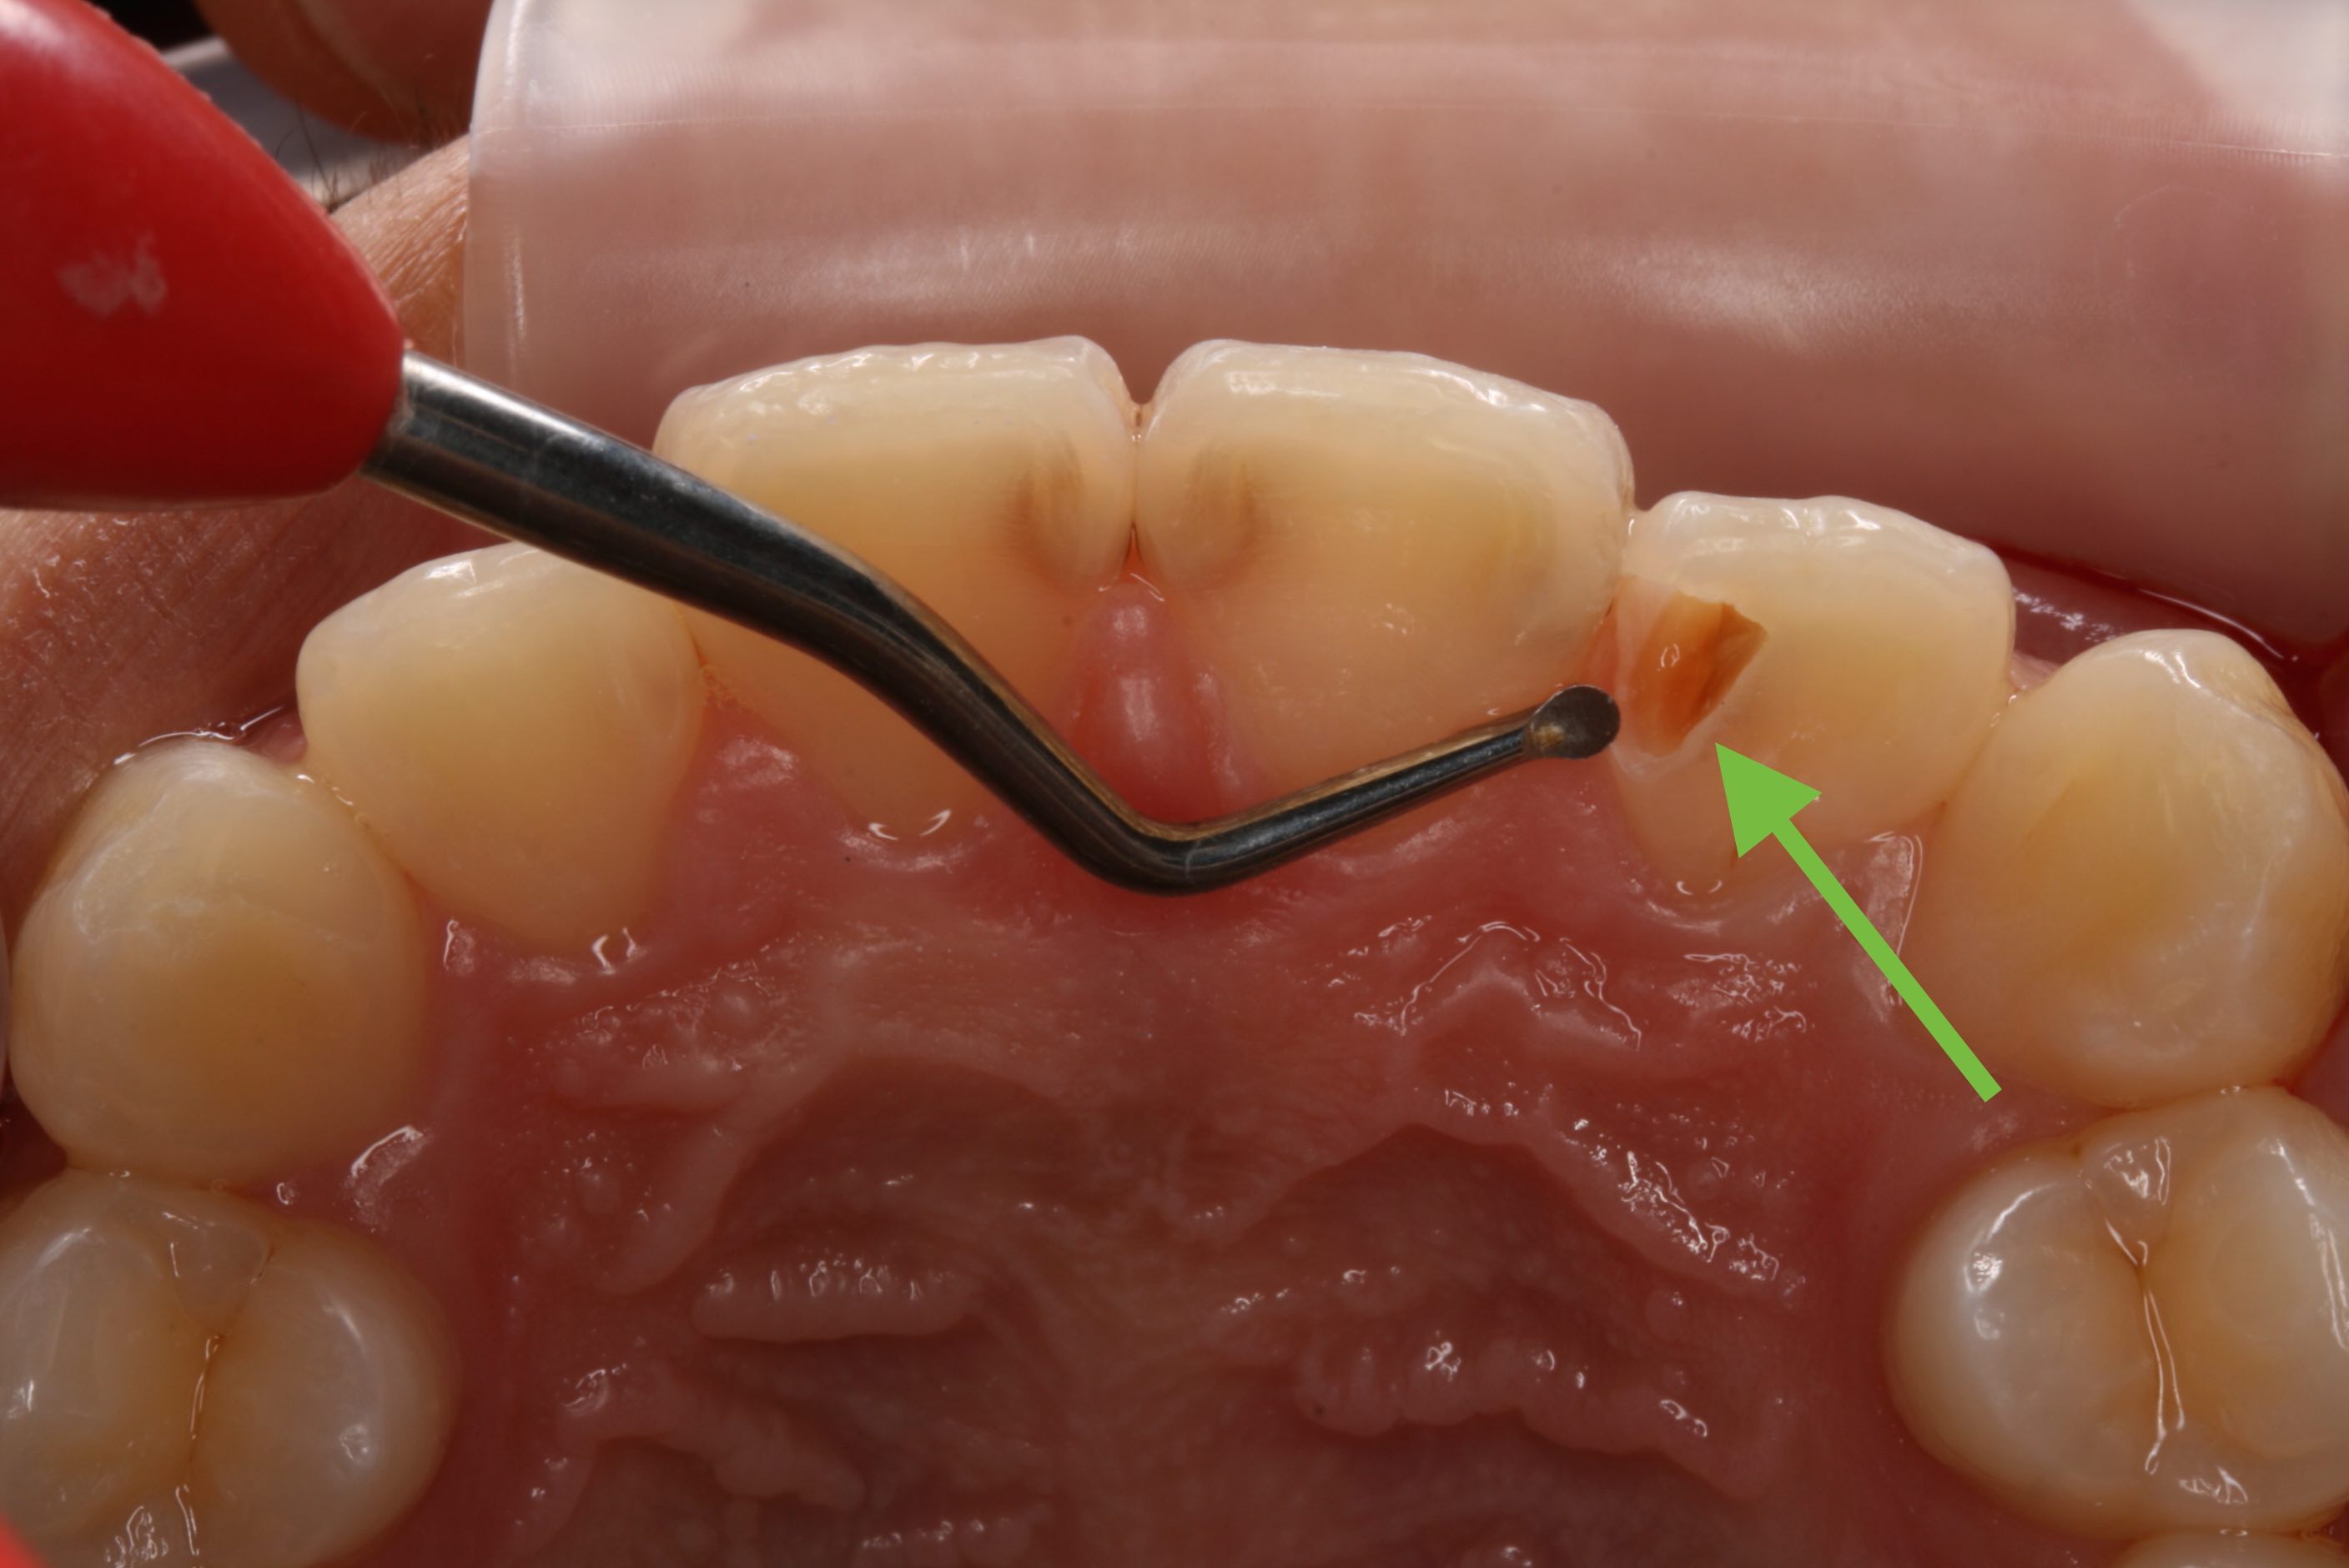

虫歯をきれいに除去したときに、神経が見えたらいつも判断に悩んでしまいます。

神経を取り除く(抜髄)か神経を温存する薬を塗る直接覆髄をするかです。

直接覆髄はあまり予後がよくありません。

そこで、意図的に虫歯を少し残して、間接的に神経を温存する薬を塗り、とりあえず歯に詰め物をして終了します。その後、定期的にレントゲンを撮影して、象牙質ができたか確認し、もう一度残してきた虫歯を取り除いて詰め物をします。薬は抗生物質(3MIX)よりもHYカルボテンポラリーソフトの方が学会のお墨付きもあり、予後が良いです。

ティーンエイジャーにおいて成功率の高い方法です。